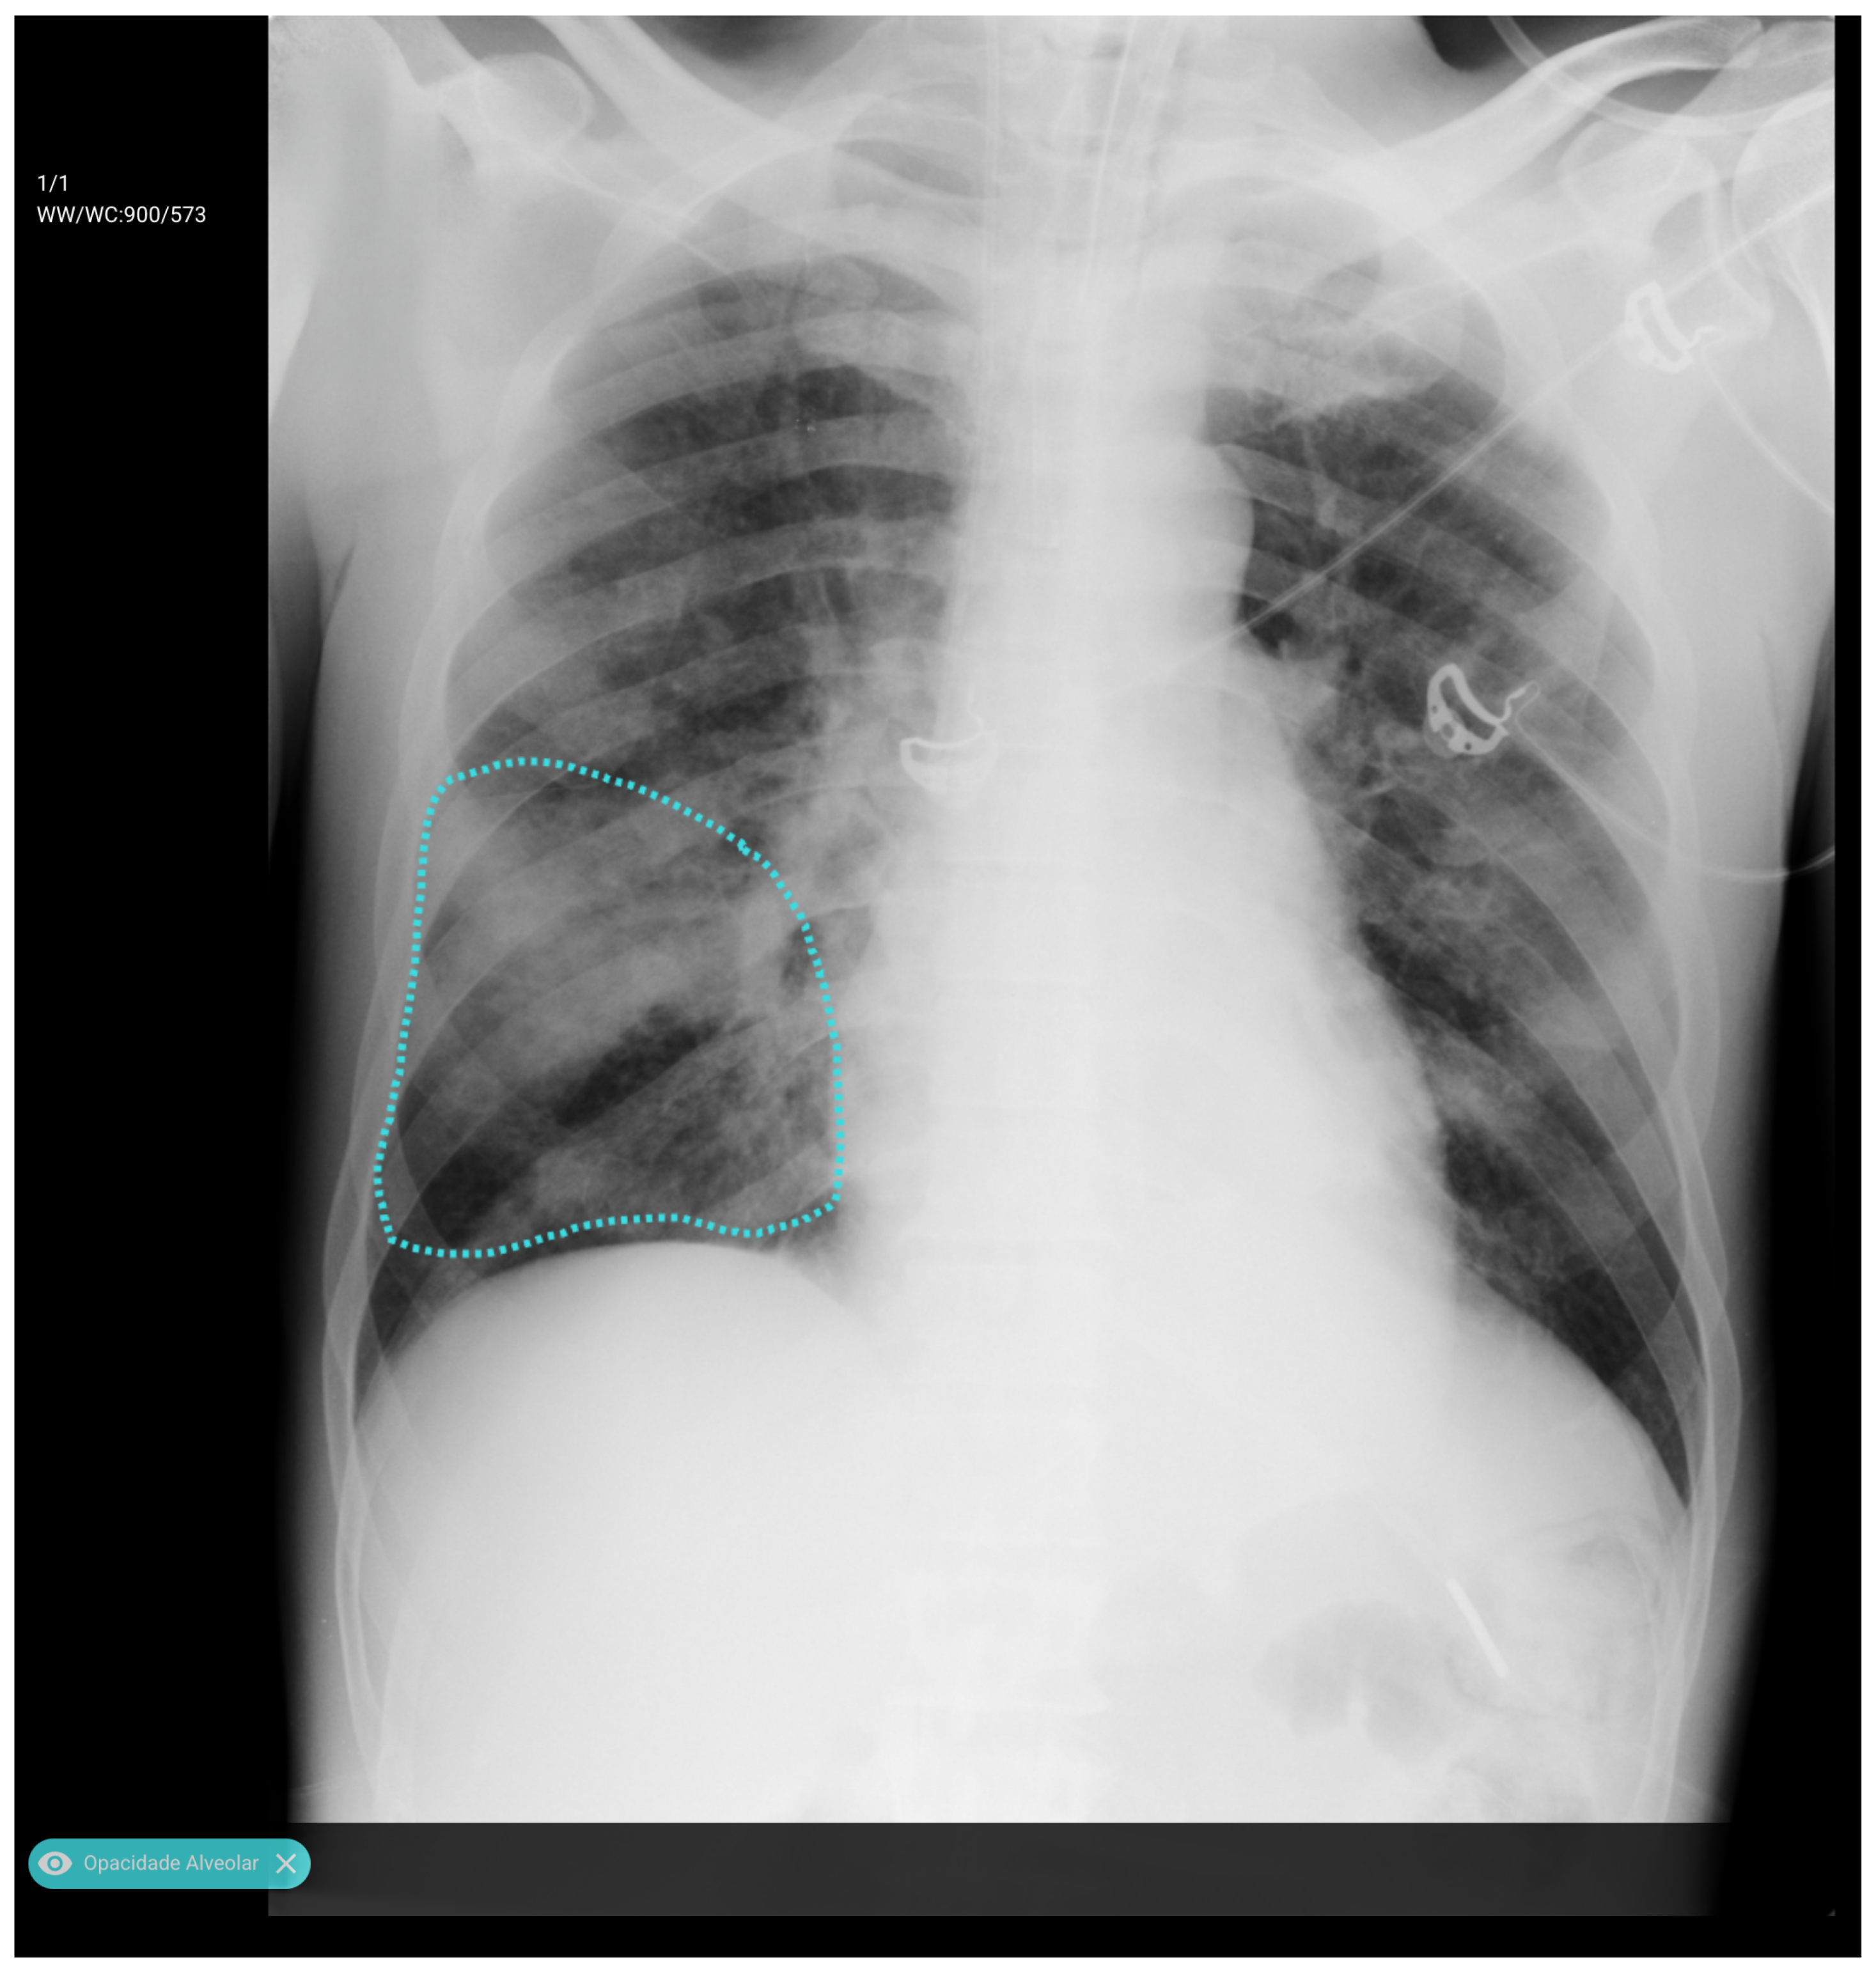

We resized input images to 512 × 512 pixels and performed data augmentation using geometric and photometric transformations (padding, Gaussian noise, CLAHE, brightness/gamma adjustment, blur, motion blur, and hue/saturation shifts). The model was trained for 40 epochs with a batch size of 8 using the Adam optimizer (initial learning rate = 5 × 10−5) and a composite loss function combining Dice loss and binary focal loss to balance region overlap and class imbalance. Performance was monitored using Intersection over Union and F-score metrics, and the best model was selected by minimizing the validation loss with adaptive learning rate scheduling. Figure 2 illustrates the resulting mask, which ensures inclusion of central thoracic structures.

Figure 2. Example of first-stage segmentation: the generated “tongue-shaped” mask covering both lungs and mediastinal structures.